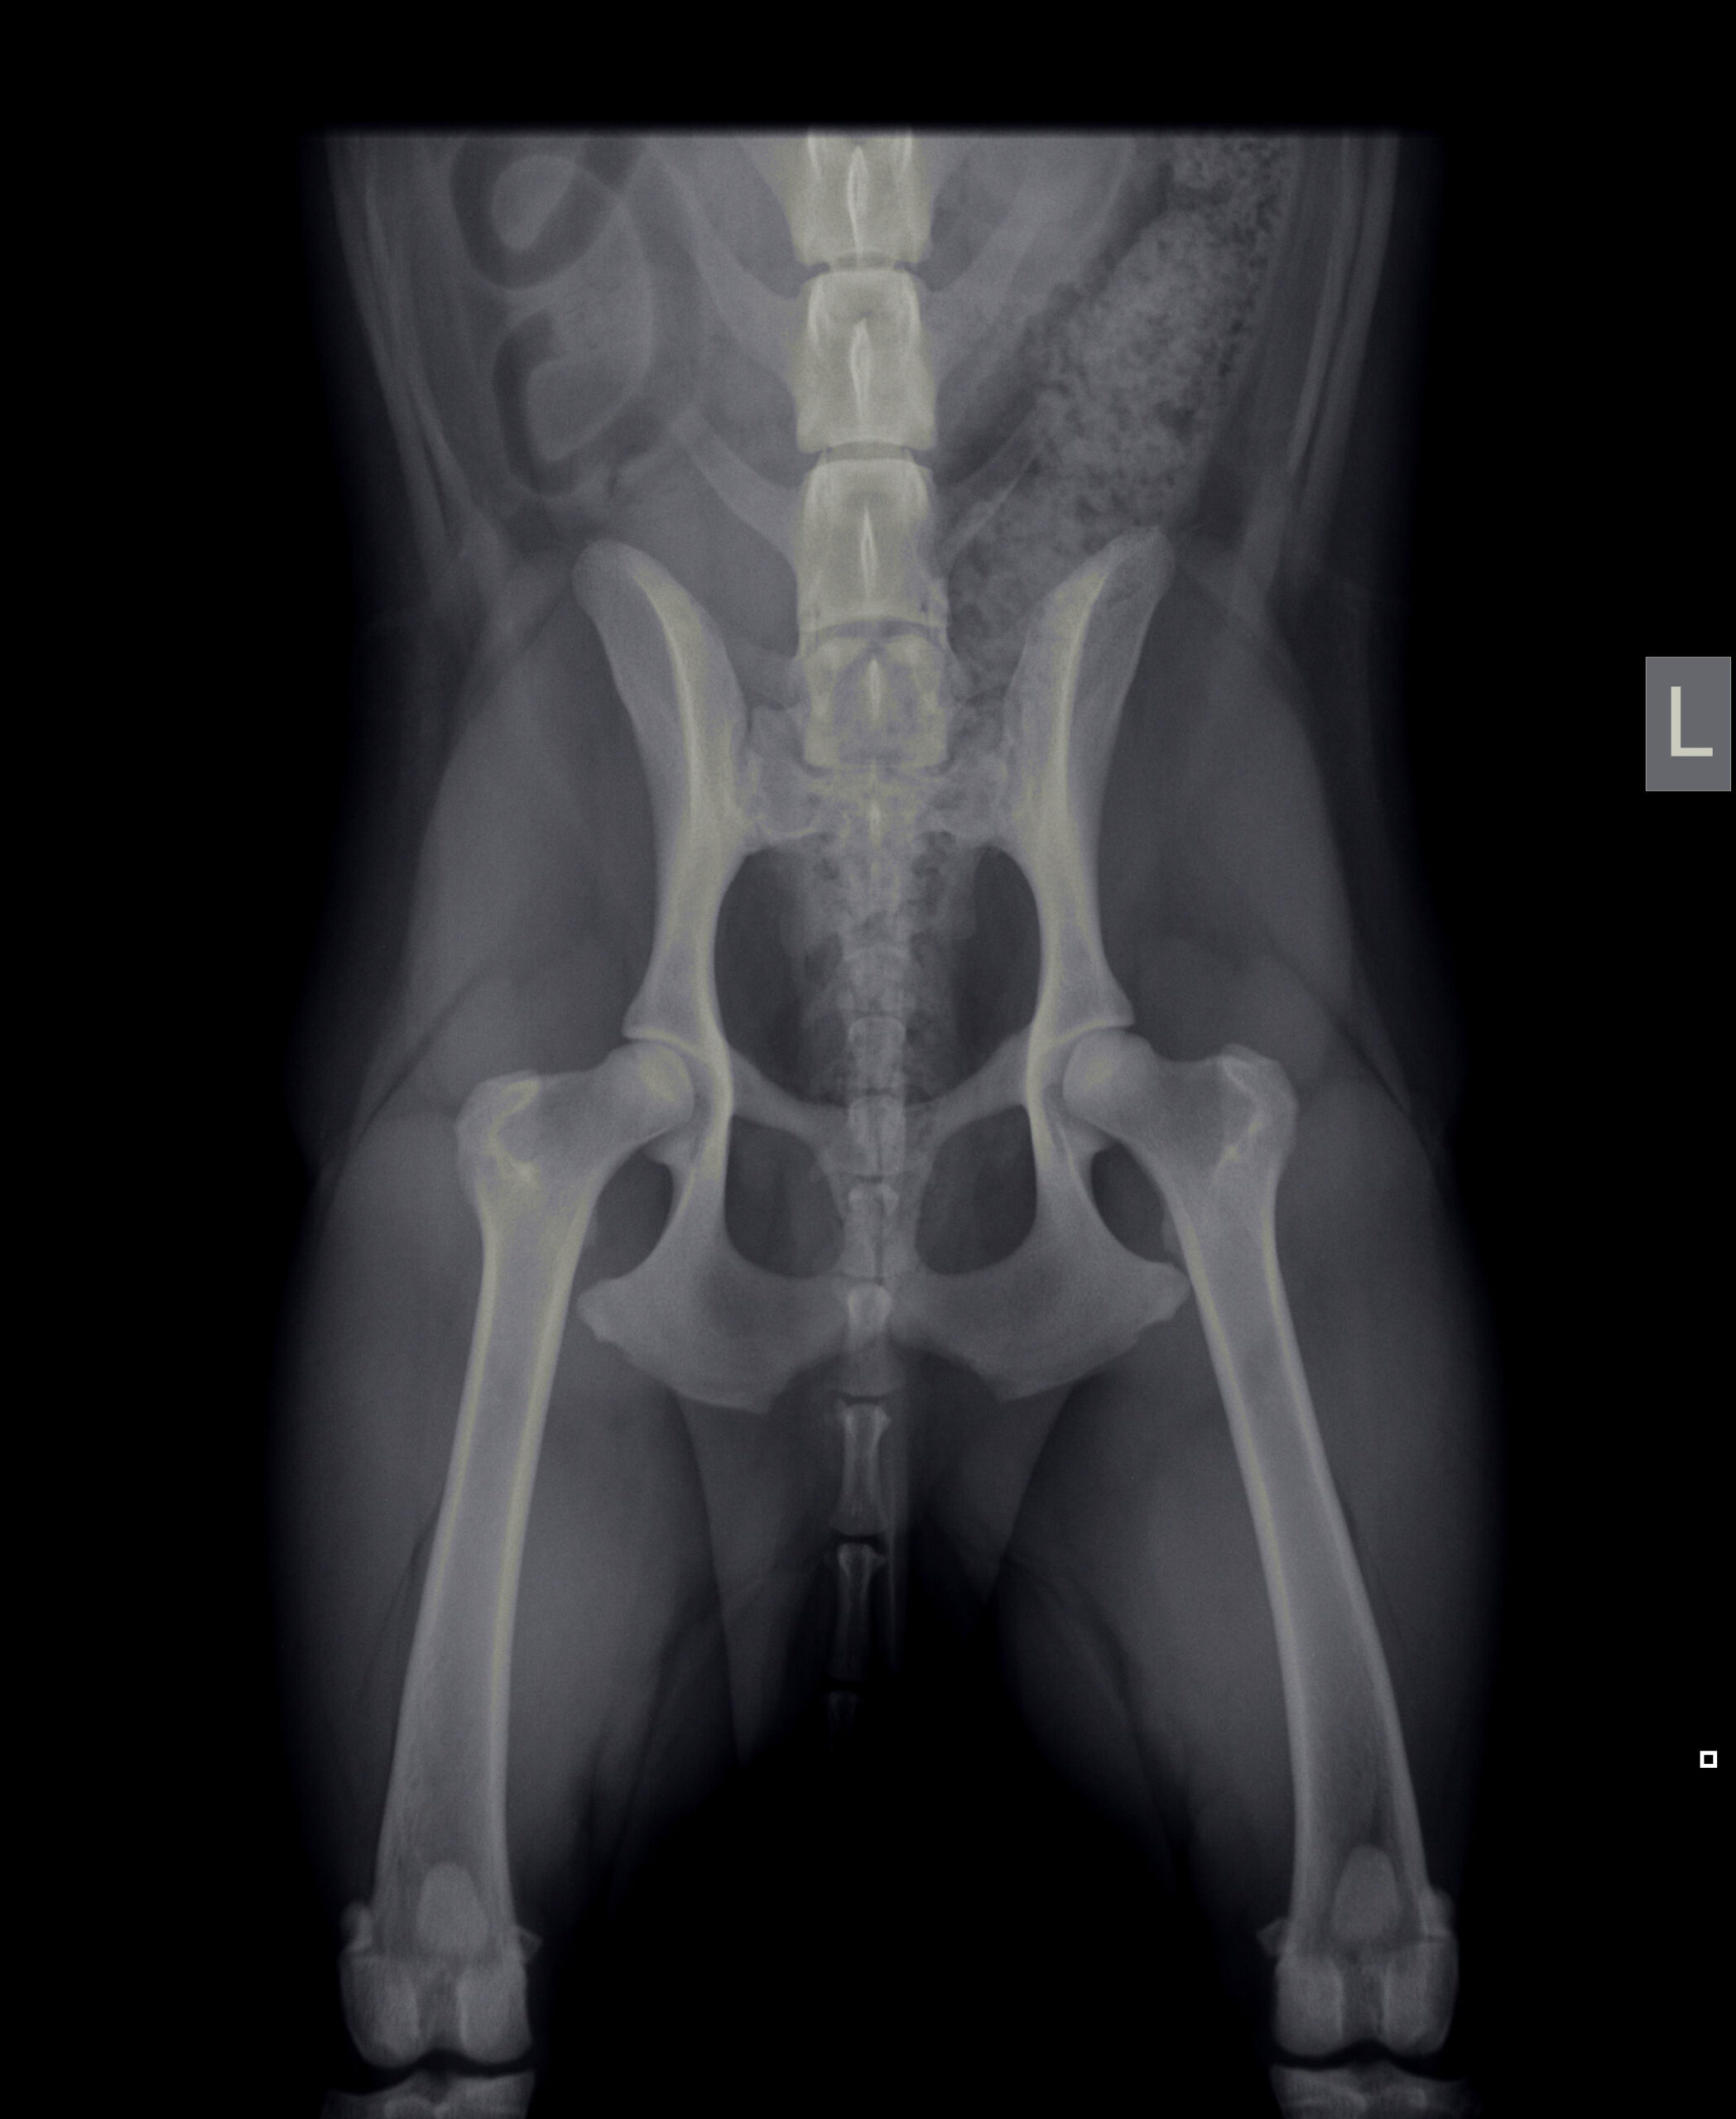

We maken ook officiële HD- en ED-foto’s, die ter beoordeling naar de Raad van Beheer worden gestuurd. Hiervoor hebben wij dan ook de stamboomgegevens van de hond nodig.